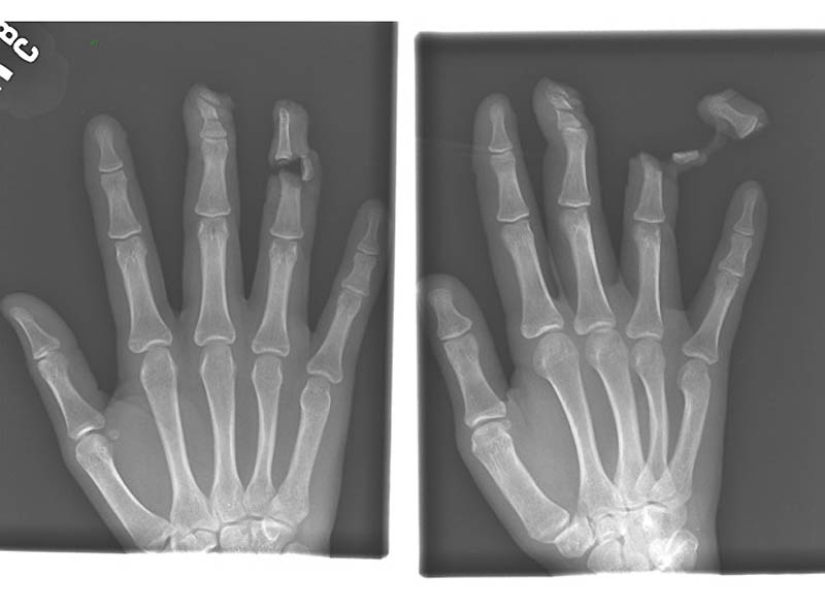

4. Uña en los huesos de los dedos índice y medio de un macho adulto.